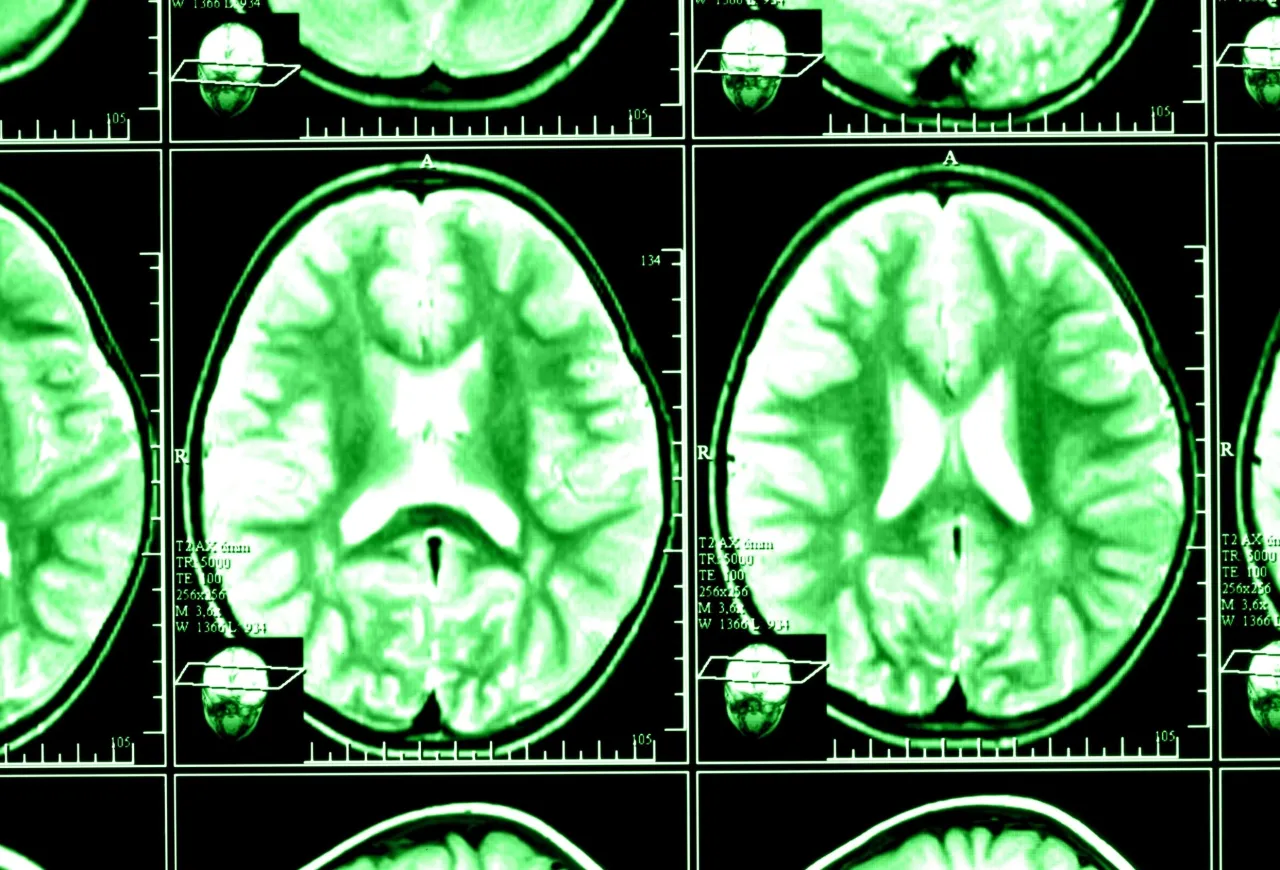

Co dokładnie „widzi” tomograf? Przewodnik po obrazach struktur mózgu i czaszki

Kiedy patrzymy na obrazy z tomografii komputerowej głowy, widzimy znacznie więcej niż tylko ogólny zarys. To, co dla niewprawnego oka może wydawać się skomplikowanym zbiorem szarości, dla radiologa jest mapą pełną szczegółów. TK głowy pozwala na precyzyjne zobrazowanie zarówno samego mózgu, jak i otaczających go struktur kostnych oraz tkanek miękkich.

Mózg w przekroju: Jak odróżnić istotę szarą od białej i co to mówi o jego stanie?

Tomografia komputerowa, dzięki różnicom w gęstości tkanek, pozwala na rozróżnienie istoty szarej od białej w mózgu, choć nie z taką precyzją jak rezonans magnetyczny. Na obrazach TK możemy dostrzec szereg patologii w obrębie mózgowia. Mówimy tu o wodogłowiu, czyli nadmiernym gromadzeniu się płynu mózgowo-rdzeniowego, ropniach mózgu, które są ogniskami infekcji, czy też o cechach zaniku kory mózgowej, co bywa widoczne na przykład w chorobie Alzheimera. Badanie to pomaga również w identyfikacji stanów zapalnych, takich jak zapalenie opon mózgowych, oraz wrodzonych wad rozwojowych mózgu. Każda z tych zmian ma swoje charakterystyczne cechy na obrazie, które doświadczony radiolog potrafi rozpoznać.Więcej niż mózg: Co TK pokazuje w zakresie kości czaszki, zatok przynosowych i oczodołów?